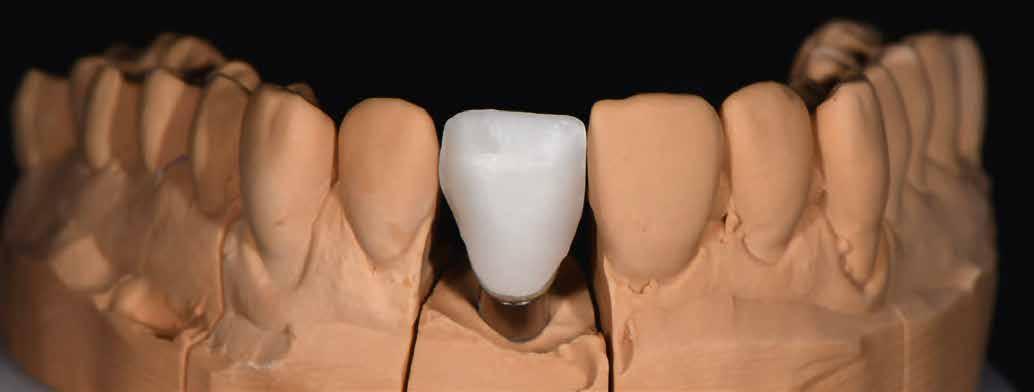

Implantátum-protetikai ellátás digitális tervezéssel

Egyetlen frontfog pótlása most is – akárcsak korábban – a királykategóriába tartozik. Bármely kis formai vagy színhiba kíméletlenül megmutatkozik minden mosolynál. Ezzel hihetetlen szintet nő, vagy csökken a páciens életminősége. Stefanie Flentje esetbemutatása ismerteti, hogyan valósíthatunk meg sikerrel implantátum elhorgonyzású borítókoronát a frontterületen.

A 64 éves hölgypáciens esztétikus pótlást kívánt 21-es foga helyén, amelyet balesetet követően 2022-ben távolítottak el. Az összes foga egészséges és vitális volt, így a 21-es régióba implantátum került, amelyre cirkónium-dioxid koronát terveztünk. Az implantátum típusát, pozícióját, átmérőjét egyedi anatómiai adottságainak és az adott helyviszonyoknak megfelelően választottuk meg.

építményhez gyári Camlog titánbázist használtunk, amit előzetesen befedtünk DCMhotbond fusio connect spray-vel. A titánbázis felületi kondicionálásához alkalmazott anyag kiváló, résmentes és tartós kötési alapot teremt a bázis és a rá készülő cirkon konstrukció között1. A cirkónium-dioxid egyedi felépítmény tervezését primer teleszkóp koronaként választottuk ki a CAD-szoftveres lehetőségek tárából. A felső mintát a beszórt titánbázissal ínymaszkkal és anélkül is beszkenneltük, akárcsak az antagonista mintát. A titánbázist hárompontos vonatkoztatással illesztettük a digitális mintába, majd megállapítottuk a behelyezési irányt és az illesztő paramétereket (7–13. képek).

Tervezés és kivitelezés a laboratóriumban

Az implantátumról készült lenyomat, valamint az alginát antagonista fertőtlenítése után szuperkemény gipszből az előírások szerint elkészültek a minták. A felső mintát a technikai implantátum körül levehető ínymaszkkal készítettük. SAM-arcív segítségével habituális okklúzióba helyeztük a mintákat. A felső mintát előkészítettük a digitális tervezéshez, enyhén megformáltuk az emergenciaprofilt, hogy tökéletes legyen a rózsa-fehér esztétika. A fogszínt – a pácienssel történt egyeztetést követően – dokumentáltuk.

Digitális tervezés

A mintát beolvastuk (D1000, 3Shape), majd megterveztük a munkát (3Shape Dental System) (6. kép). A fel -